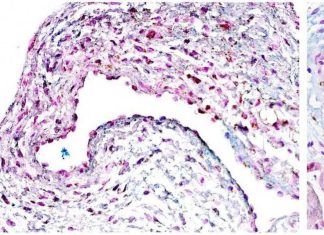

Reportajes

CHILE IMPULSA NUEVOS AVANCES EN INVESTIGACIÓN CLÍNICA EN CÁNCER DE PULMÓN,...

Portal Red Salud | Grupo Prensa Digital | jv

-

noviembre 4, 2025

0